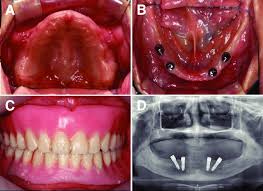

Full mouth reconstruction, rehabilitation and restoration are terms often used interchangeably to describe the process of rebuilding or simultaneously restoring all of the teeth in both the upper and.

Day of surgery full mouth extractions. Full mouth dental implants are your best lifelong investment. I am 55yo and have only 20 teeth in my mouth. In the case where a full mouth extraction is necessary, know that your cat can still lead a happy and healthy life including properly eating. Earlier studies with low number of patients have shown. He had in fact 3 different extractions. Atraumatic extraction procedure performed with the physics forceps by golden dental solutions. Full recovery from the surgery can take about a week, sometimes more, depending upon a patients age and if they undergo a full or. Full mouth extraction day 3. How long before pain goes away from full mouth teeth extraction? This little fella had to get a full mouth extraction from a lifetime of rotted teeth. · the day of your surgery. Full mouth reconstruction, rehabilitation and restoration are terms often used interchangeably to describe the process of rebuilding or simultaneously restoring all of the teeth in both the upper and.

Socket preservation / grafting is performed followed by immediate. Gingivalis in 15 of 16 and 8 of 16 previously positive patients using. While having all of your teeth pulled at once can seem like something nobody wants to go through, a lot of the time it's for your best interest and to provide you. You might come across a bump or sore in your mouth that doesn't seem to heal. This is just a little video about my experience with a full mouth extraction.

Full mouth disinfection typically refers to an intense course of treatment for periodontitis typically involving scaling and root planing in combination with adjunctive use of local antimicrobial adjuncts to periodontal treatment such as chlorhexidine in various ways of application. · precautions that should always be taken after the procedure. This is just a little video about my experience with a full mouth extraction. Day 4 and 5 full mouth extraction. Full mouth extraction recovery process. Full mouth dental implants are your best lifelong investment. The vet says his left side is worse than the right but he needs a full mouth extraction. In the case where a full mouth extraction is necessary, know that your cat can still lead a happy and healthy life including properly eating. Grigsby asked that his wife come to the treatment room where they discussed the options. Gingivalis in 15 of 16 and 8 of 16 previously positive patients using. Dentistry by tim kosinski dds, bingham farms mi. Full mouth reconstruction, rehabilitation and restoration are terms often used interchangeably to describe the process of rebuilding or simultaneously restoring all of the teeth in both the upper and. $524 raised of $1,000 goal.